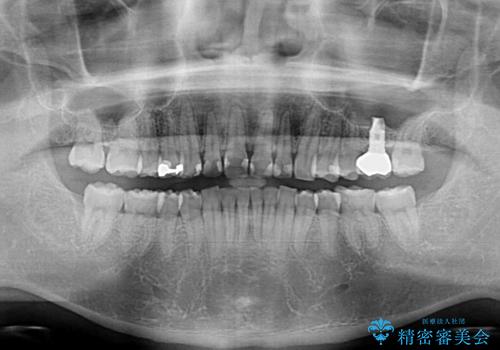

- 深い咬み合わせと前歯のデコボコ、奥歯の欠損を気にして来院された患者様です。

歯列矯正はインビザラインを使用し、矯正治療中の適切な時期に奥歯の欠損部位にインプラントを埋入することとしました。